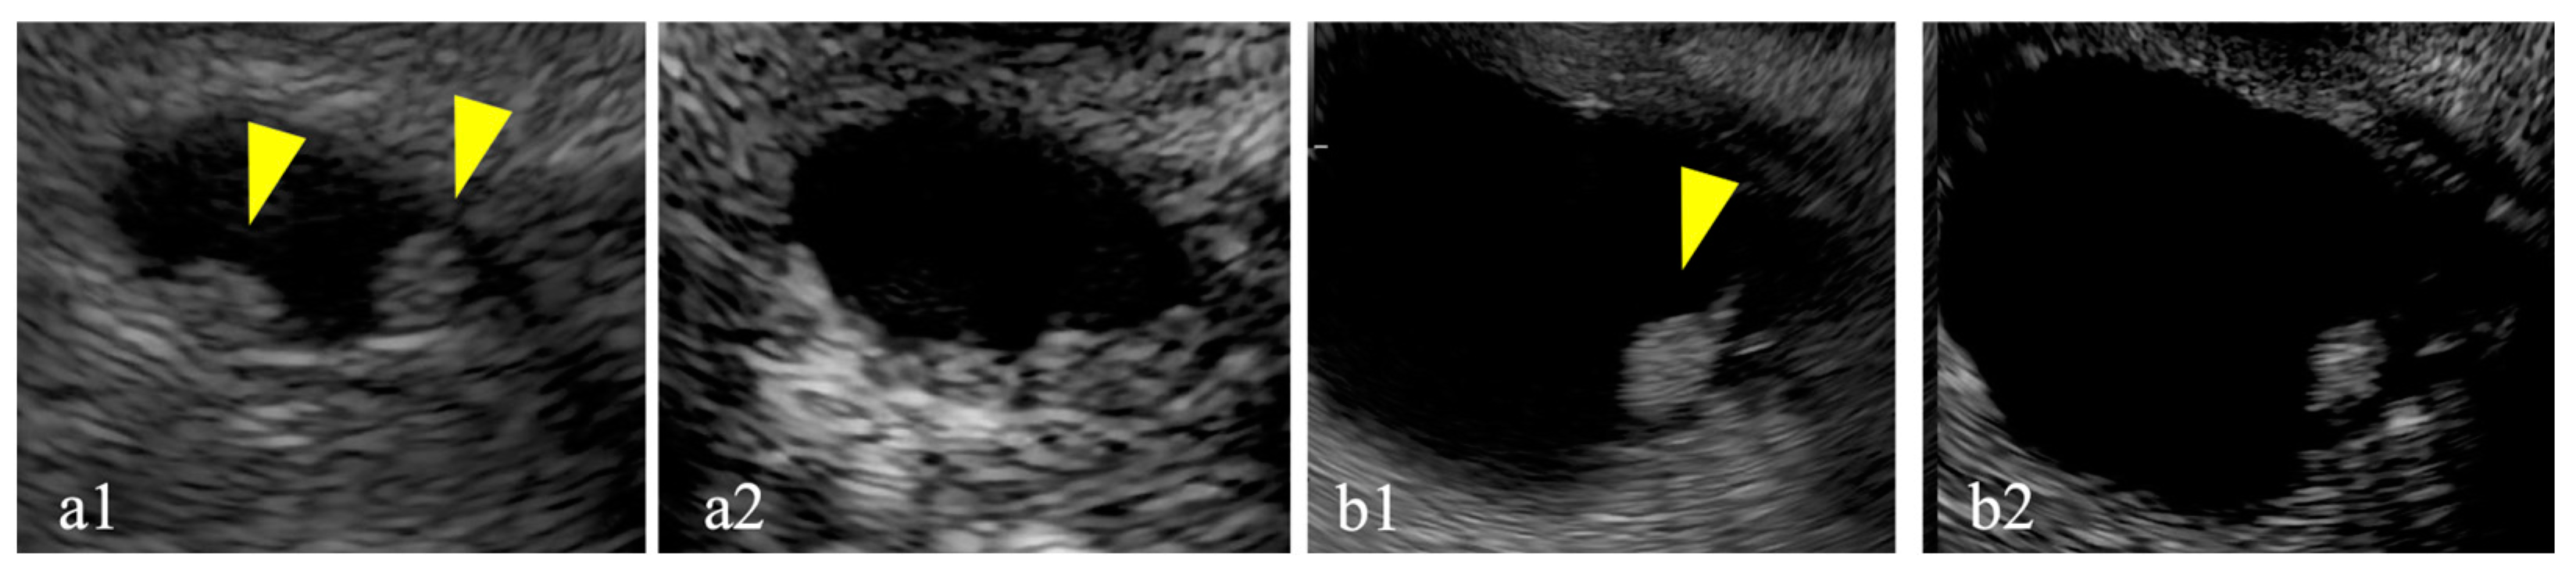

3.4. Diagnostic Accuracy of DFI-EUS

Figure 4. Detective flow imaging (DFI) and contrast-enhanced (CE) endoscopic ultrasonography (EUS) images of mural nodules smaller than 10 mm. Case 1 is observed using DFI-EUS (yellow arrow; a1) and CE-EUS (a2). Case 2 is observed using DFI-EUS (yellow arrow; b1) and CE-EUS (b2). Case 3 is observed using DFI-EUS (yellow arrow; c1) and CE-EUS (c2). DFI-EUS images of linear or dotted vessels inside the mural nodules. All CE-EUS images show homogeneous enhancement.